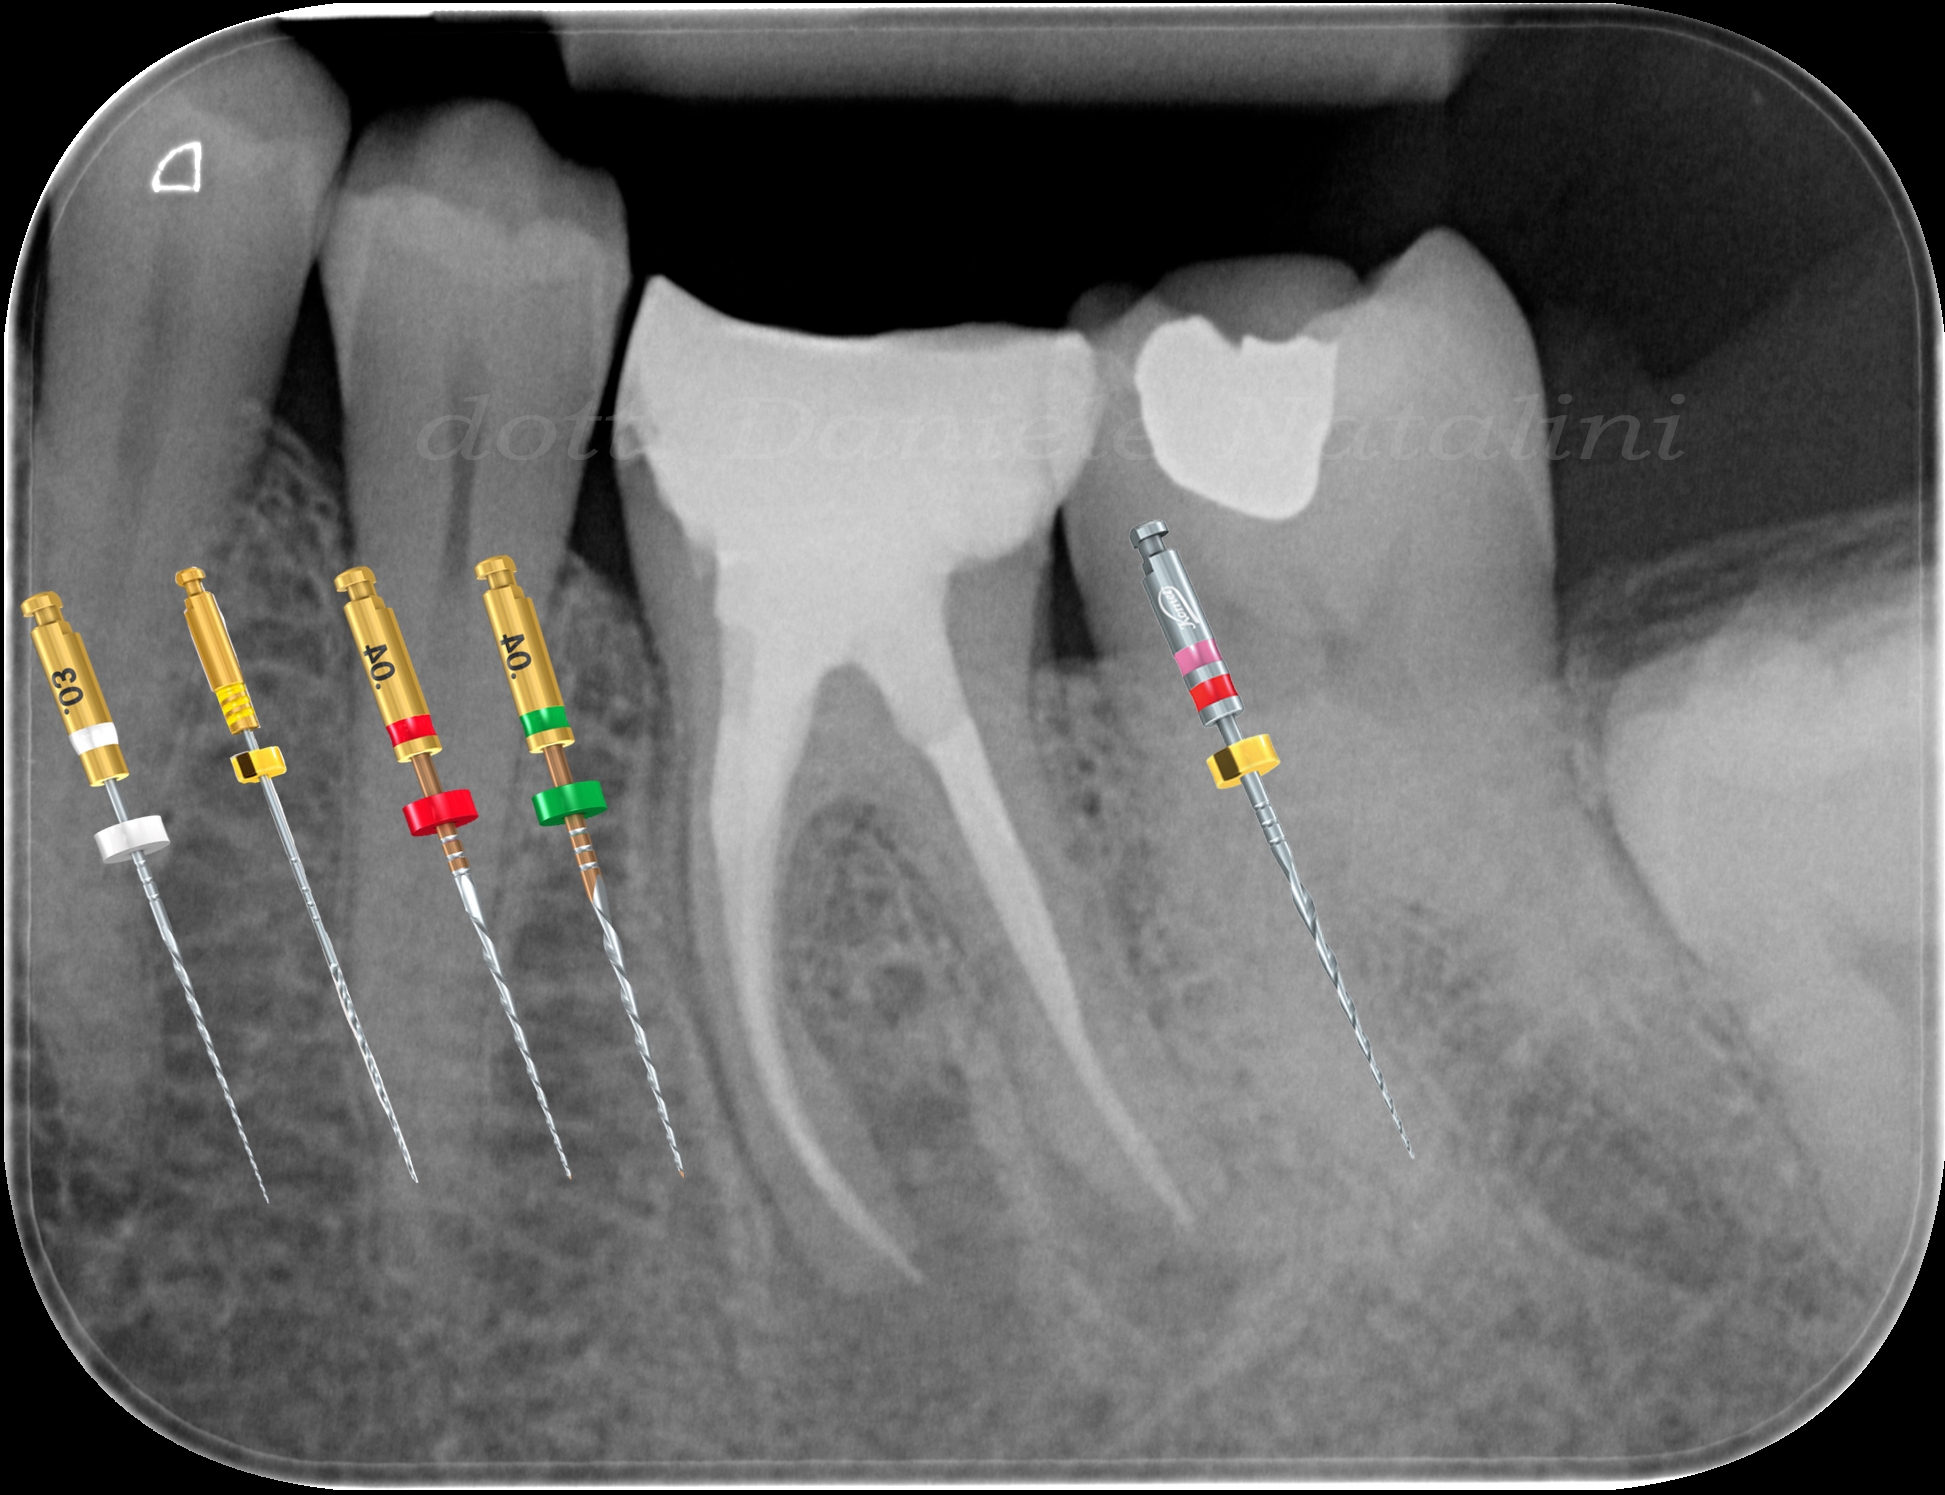

La strumentazione Komet da PathGlider FQ 15/03 e 20/03, a FQ Files 25/04 fino al 35/04, a mio avviso sono efficaci sia come diametri apicali finali, sia per la conservativa nei confronti dei diametri più coronali. Un aiuto nella rimozione del materiale residuo dai canali è arrivato dallo strumento Endo ReStart.

È stata eseguita una chiusura "differenziata": Bioceramico Komet Bioaseal e cono singolo 35/04 nel mesiale (più il suo confluente) per impossibilità di oltrepassare la ristretta curva a livello del terzo medio con portatore di calore e plugger; al contrario, nel distale, dove invece era possibile, guttaperca e pulp canal sealer con verticale a caldo. Ricostruzione definitiva con flow e composito G-Aenial GC e finalizzazione protesica con corona in zirconia Katana 600.